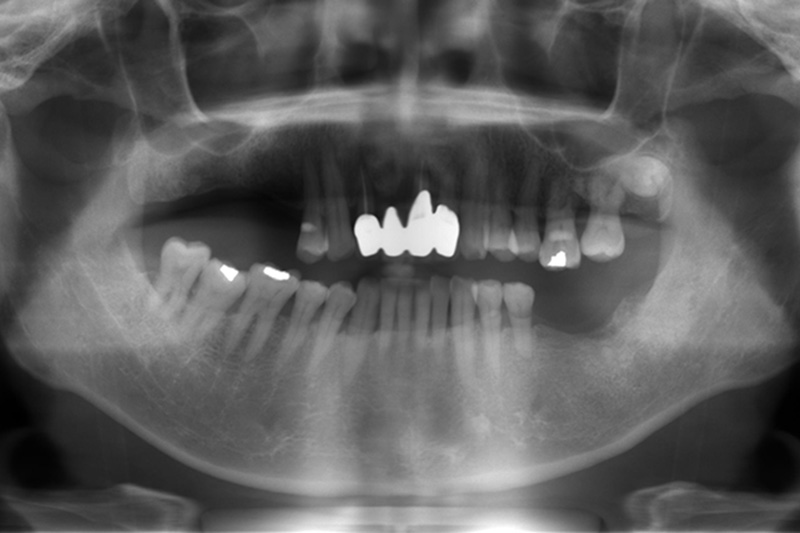

水雷射植牙重建 首頁 案例分享 植牙 水雷射植牙重建 水雷射植牙重建 案例A 治療前 治療後 聲明:本所療程皆由專業醫生評估後,依照個人口腔狀況進行治療。因每位患者個別狀況不同,術後狀況也不盡相同,需親來本所由醫生評估。